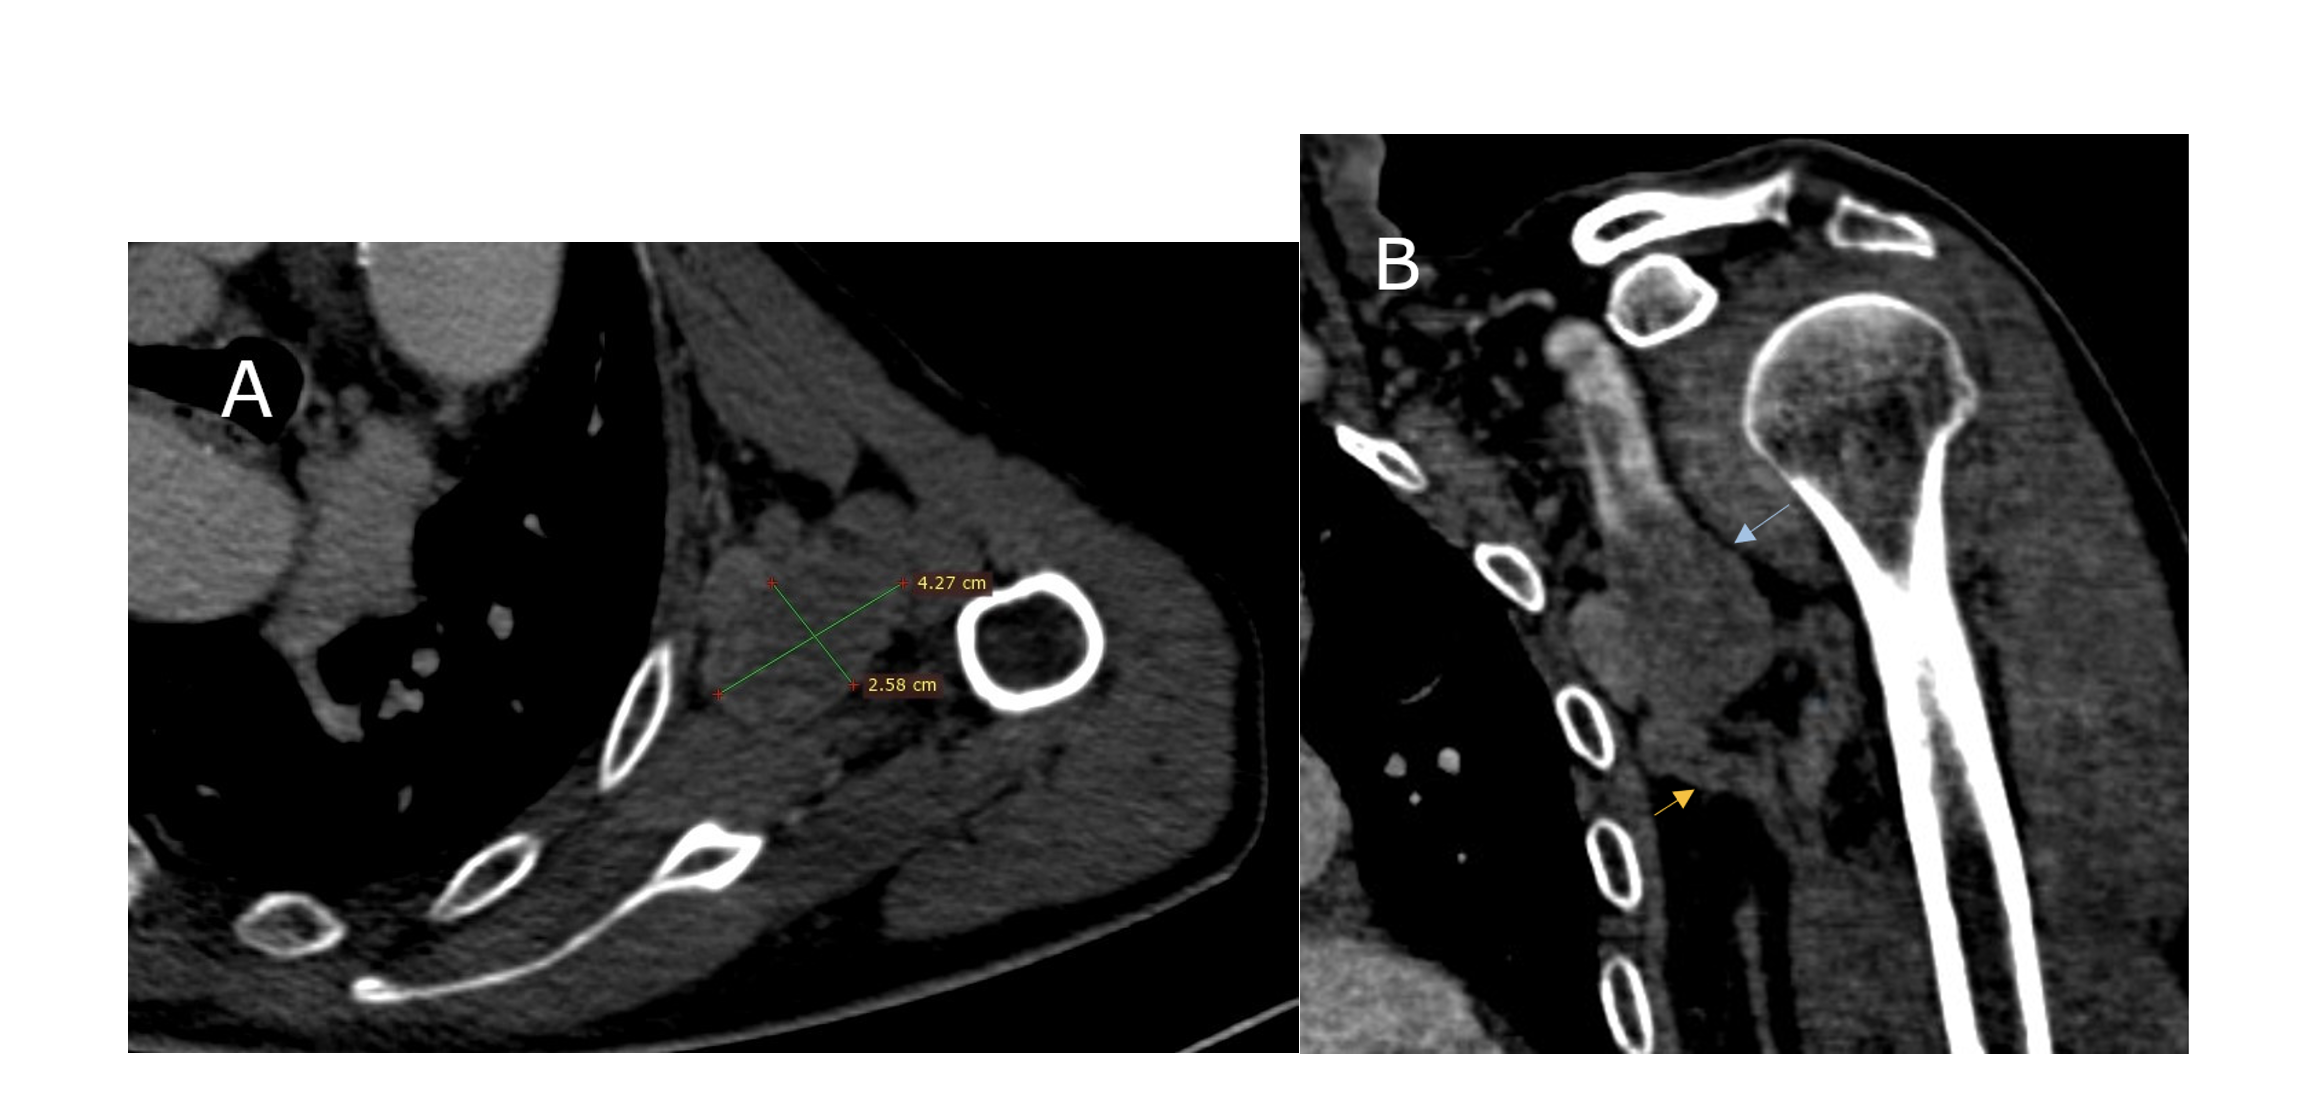

An 87-year-old man presented to the emergency department with the complaint of increasing pain and numbness in his left forearm, associated with cyanosis of the tips of the fingers of his left hand evolving since the day before (Figure 1). He had no history of trauma or vascular intervention, but he was hypertensive and receiving oral anticoagulation therapy for chronic atrial fibrillation. No axillary mass was seen in the physical examination; however, humeral, ulnar, and radial pulses were absent and a neurological examination of the upper extremity showed paresthesia of the fingers. His body temperature was within normal limits but his left upper limb was cold. Computed tomography angiography (CTA) showed a completely thrombosed fusiform aneurysm of the left axillary artery with a dimension of 4.2 cm x 2.4 cm. (Figure 2A and B). The distal arteries were not contrasted; we immediately started intravenous heparin, and urgent open surgical resection of the aneurysm was planned. Under general anesthesia and through an infraclavicular incision, we controlled the axillary artery upstream from the aneurysm, then the brachial artery after a brachial approach. The aneurysmal mass was carefully dissected and separated from the surrounding tissues. Care was taken not to injure the brachial plexus. After thrombectomy of the brachial, radial, and ulnar arteries using a Fogarty arterial embolectomy catheter (Edwards Lifesciences), we completely resected the aneurysm. Arterial continuity was established with an 8-mm ringed polytetrafluorethylene (PTFE) graft from the infraclavicular axillary artery to the proximal brachial artery, as the saphenous vein was of inadequate quality. Distal and proximal anastomosis were done in an end-to-end fashion. Distal pulses were normal after the anastomosis, and no complications occurred during the procedure. A pathological examination of the aneurysm sac revealed a true axillary artery aneurysm on an atherosclerosis basis. The postoperative course was uneventful, the patient’s symptoms improved, and he was discharged on the third postoperative day without sequelae.